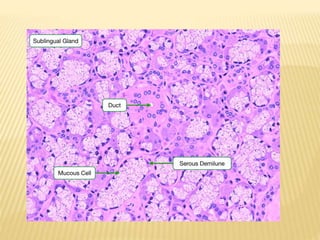

SUBLINGAUL GLAND

SEROUS ACINI MUCOUS ACINI MIXED ACINI

AS SEROUS DEMIUNES

MUCOUS ACINI

 Have serous associated

them in form of demilunes.